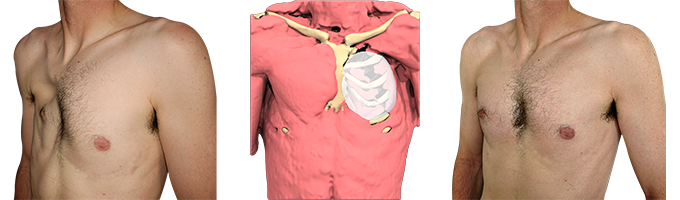

Im Alter von 33 Jahren suchte die Patientin Dr. Schirmer auf, weil das Ergebnis der ersten Operation als unzureichend empfunden wurde. Die klinische Untersuchung zeigte eine persistierende Deformität, die durch das Fehlen des Musculus pectoralis major und eine retraktile Hülle, die das Brustimplantat deformierte, verursacht wurde. Die Narbe ist unansehnlich.

- Einbau eines maßgefertigten Elastomerimplantats, das mittels computergestütztem Design (CAD) hergestellt wurde,

- Positionierung des maßgefertigten Implantats, wobei die alte Brustprothese und die dicke Faserkapsel, die sie umgibt, davor liegen bleiben,